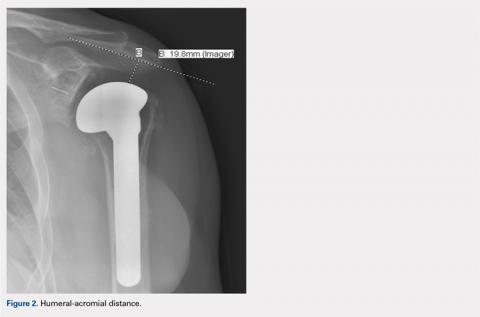

HAD was measured preoperatively, immediately postoperatively, and at final follow-up at a minimum of 1 year. The HAD was measured from the lowest point on the acromion to the humerus using a perpendicular line (Figure 2).